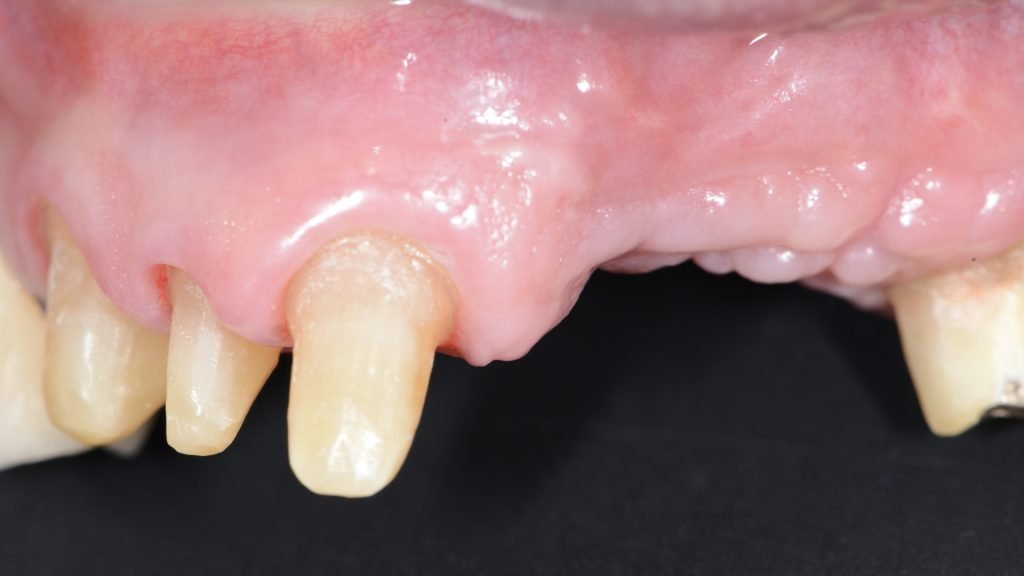

A la exploración clínica presenta implantes en posición de 21, 22 y 23 con una prótesis ceramo-metálica cementada con encía rosa donde se pueden apreciar las superficies de los implantes expuestas al medio oral (Figura 1).

- Se realizó una primera intervención quirúrgica en la que de inicio se realizó la retirada de la prótesis cementada y la explantación de los implantes en posición de 21, 22 y 23 y se realizó un injerto de tejido conectivo para sellar los lechos de los 3 implantes recién explantados (Figura 3).